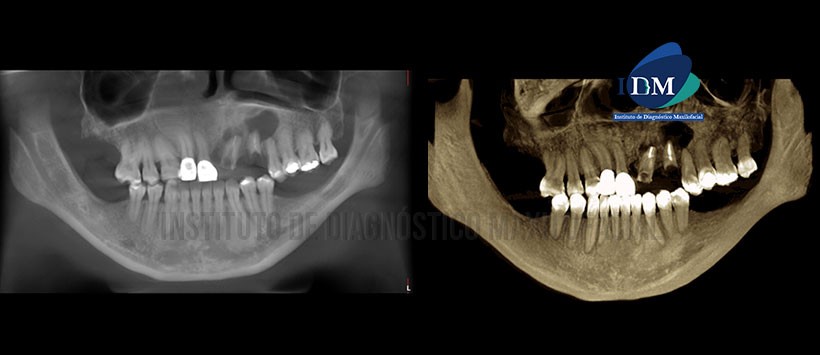

En la reformación panorámica (Figura 1) se observa imágenes hipodensas de limites definidos asociados a los ápices de piezas 21 y 23.

A la evaluación de la tomografía volumétrica (CBCT) cortes axiales (Figura 2), transaxiales (Figura 3) y tangenciales (Figura 4),  se aprecia a las piezas 21 y 23 remanentes radiculares con material de obturación de conductos. Se aprecia dos imágenes hipodensas de forma redondeada y limites definidos asociados a nivel apical de piezas 21 y 23. Lesión de pieza 21,presenta bordes corticalizados, ocasiona el desplazamiento y adelgazamiento de la tabla ósea vestibular, presenta un volumen de 0,140 cm3 (Ver figura 5). La lesión de la pieza 23 es de un tamaño mayor y ocasiona el desplazamiento, adelgazamiento y erosión de ambas tablas óseas, con extensión al piso de fosa nasal, presenta un volumen de 1,395 cm3. (Ver figura 5).